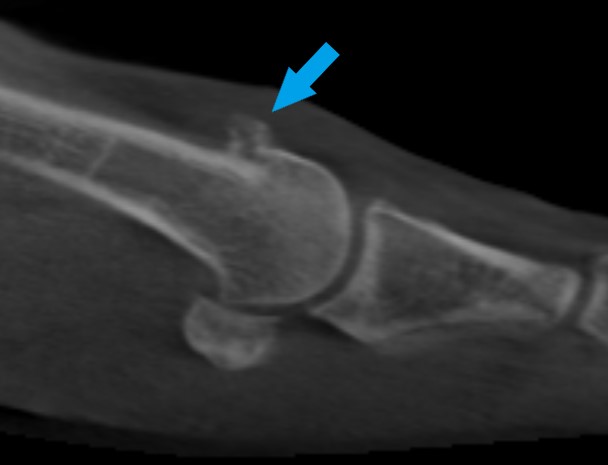

Home Schwerpunkte Krankheitsbilder Arthrose der Großzehe (Hallux Rigidus) Beginnende GGG Arthrose nach einem Unfall – gute Indikation zur Cheilektomie

Beginnende GGG Arthrose nach einem Unfall – gute Indikation zur Cheilektomie